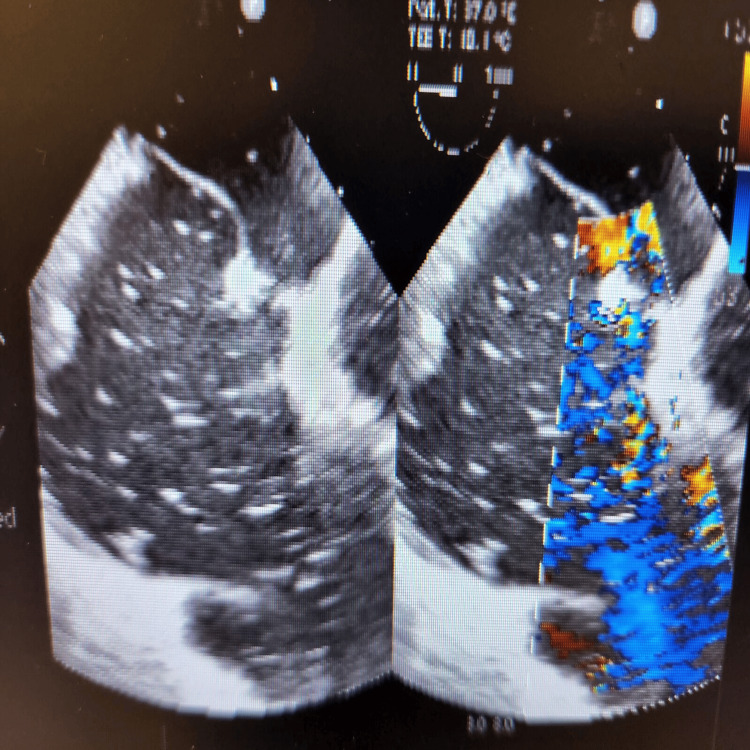

During the final stages of the ERCP procedure, a significant decrease in oxygen saturation and the emergence of irregular heartbeats were noticed. An intraoperative trans-esophageal echocardiogram (echo) revealed numerous air pockets in the right atrium, right ventricle, and left ventricle. Importantly, a patent foramen ovale was detected as shown in Figure 2, with indications of air bubbles (seen as white spots on 2D echo) passing through it into the left side of the heart as seen in Figures 3, 4. The patient was intubated in response to decreased oxygen levels while still in the operating room.

Gas embolism during ERCP is a rare but potentially fatal complication. It occurs when air enters the systemic circulation, leading to cardiovascular and pulmonary complications. One possible mechanism of gas embolism during ERCP is the intramural dissection of insufflated air into the portal venous system during endoscopic sphincterotomy [ref. 5]. In the presented case, the presence of a patent foramen ovale allowed for the passage of air bubbles from the right side of the heart to the left side, leading to systemic circulation and causing cardiovascular complications [ref. 2]. The patient’s case is unique because it involves a cardiac air embolism leading to difficulties during ERCP, which is an uncommon complication. The presence of a patent foramen ovale further complicates the situation, as it allows for the passage of air bubbles into the left side of the heart, increasing the risk of systemic complications.